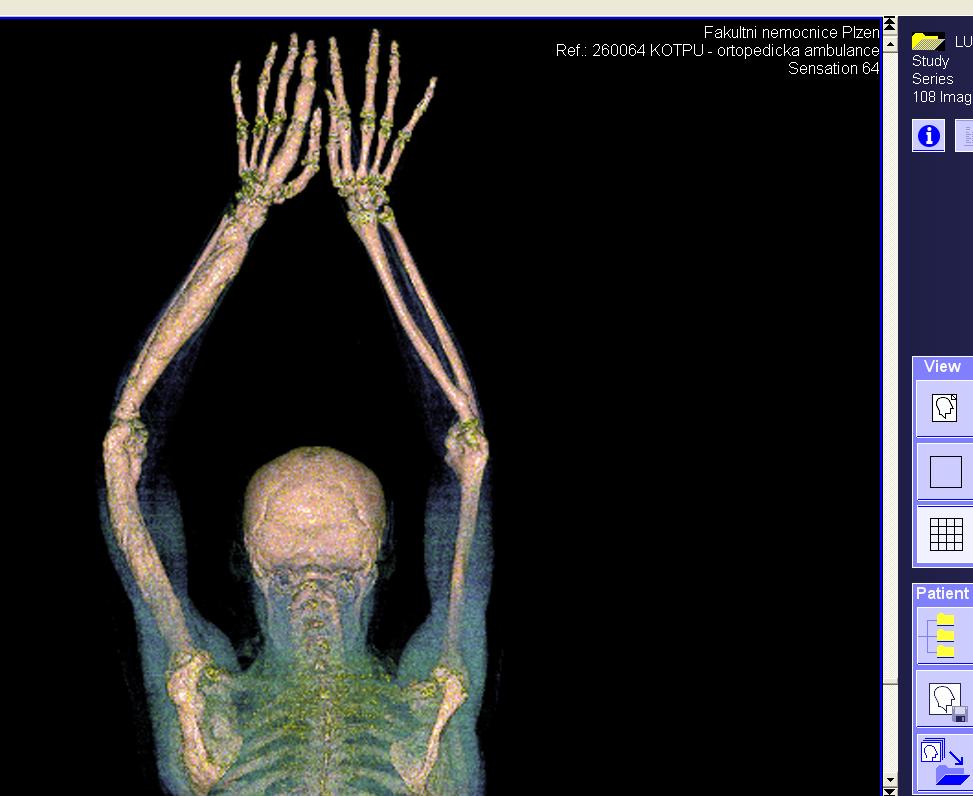

Area(s) affected:  Left arm and hand

I am sending you some photos from RTG and CT and scinti scam from last month.